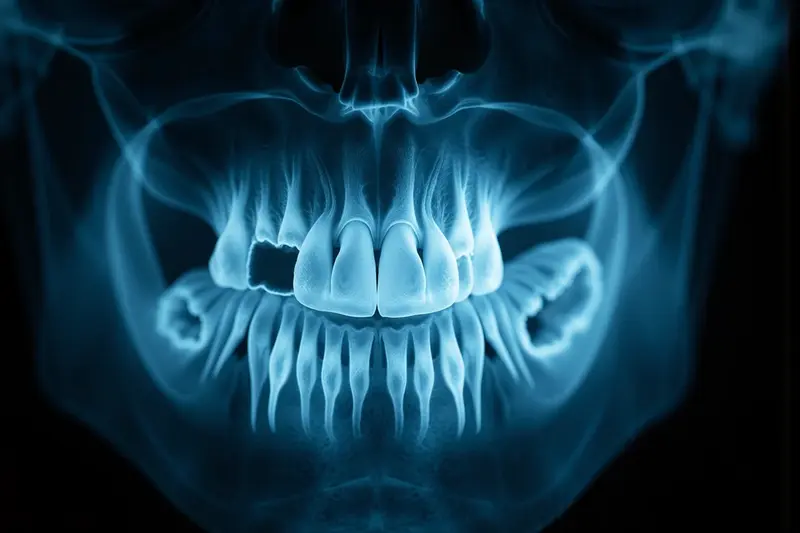

RTG jest bardzo skuteczne w wykrywaniu próchnicy międzyzębowej i wtórnej. Może być mniej skuteczne przy bardzo wczesnych zmianach szkliwa. Czasem potrzebne s...

Ząb 6 dolny zwykle ma dwa korzenie: korzeń przedni (mesialny) i korzeń tylny (dystalny).